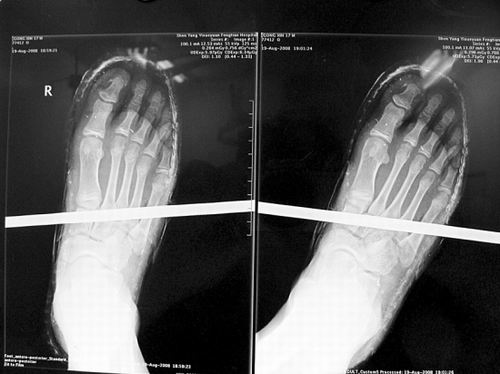

X光片顯示無大礙

事發時男孩穿著一雙布鞋,骨外二科陳賓醫生操起剪刀,將布鞋一塊塊剪掉。經X光透視,醫生驚奇地發現:男孩雖然被鋼筋穿透了右腳,但骨頭、大的血管和神經都沒受任何傷害!

20日,記者從X光片子上看到,鋼筋避開了男孩腳掌骨頭密集的部位,而是從腳弓處穿過,這個部位基本上以軟組織為主。“真沒想到,太神奇了!”幾名醫生連聲感嘆,術中,他們分工合作,小心翼翼地將鋼筋取出,并做了引流、清創、包扎。